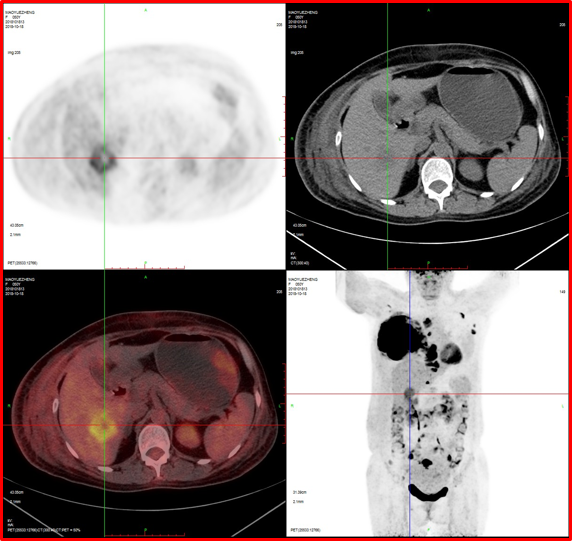

2、肝臟轉(zhuǎn)移。